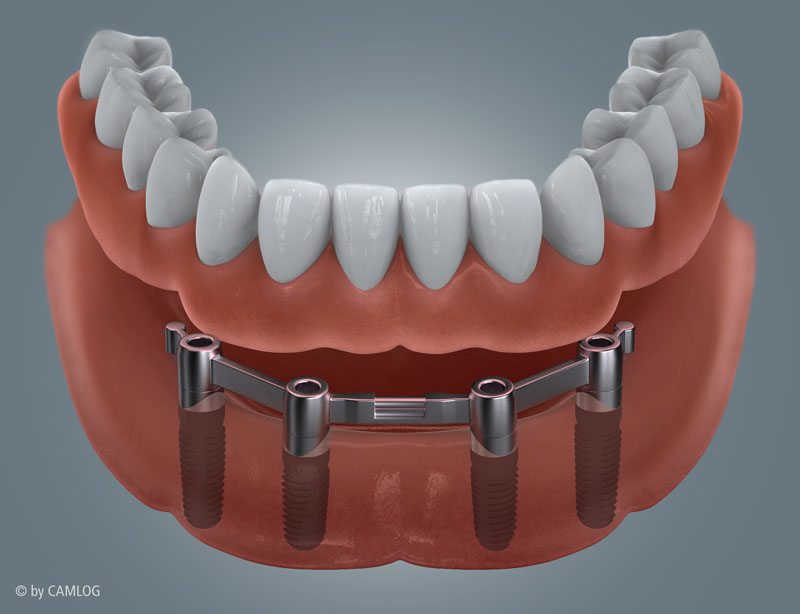

Zahnloser Unterkiefer mit Locatorversorgung

Zahnloser Unterkiefer mit Stegversorgung